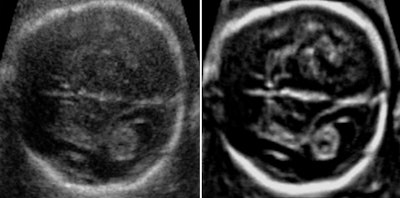

In fetal brain examinations, 3D imaging provides a full volume of the fetal brain. Adaptive volume enhancement and true-to-data rendering -- which combines adaptive volume enhancement, scan conversion, and rendering to yield high resolution and fewer image approximations -- can also improve clinical value and make it easier to perform the study. 3D ultrasound fetal brain measurements are more accurate and reproducible than their 2D counterparts, according to Selbing.